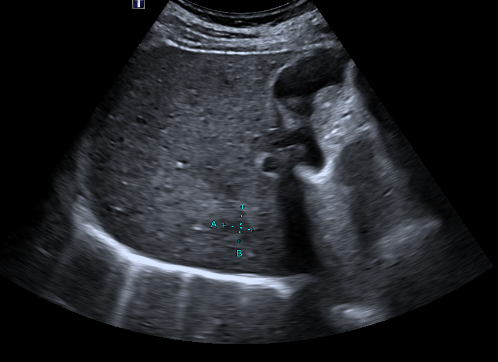

前段时间会诊了一名因为发热入院的老年患者,住院期间做胸部CT发现肝占位,因为既往有肺癌手术史,不排除肺癌肝转移,所以请肝胆外科会诊。经过肝脏超声等进一步检查(图1),考虑为肝脓肿可能性大,给予抗感染治疗后症状缓解后出院,5个月后复查,肝脓肿明显缩小(图2)。

图2:超声可见肝脓肿范围缩小至1.5cmx1.3cm